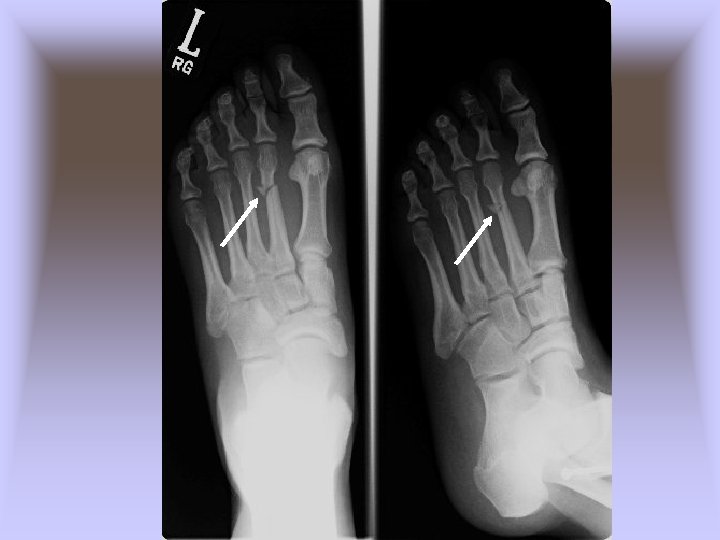

• Jones Fracture – Cause of Injury • Fracture of metatarsal caused by inversion or high velocity rotational forces • Most common = base of 5 th metatarsal – Sign of Injury • Immediate swelling, pain over 5 th metatarsal • May feel a “pop” • High nonunion rate and course of healing is unpredictable – Care • Generally requires 6 -8 weeks non-weight bearing with short leg cast if non-displaced • If nonunion occurs, internal fixation may be required